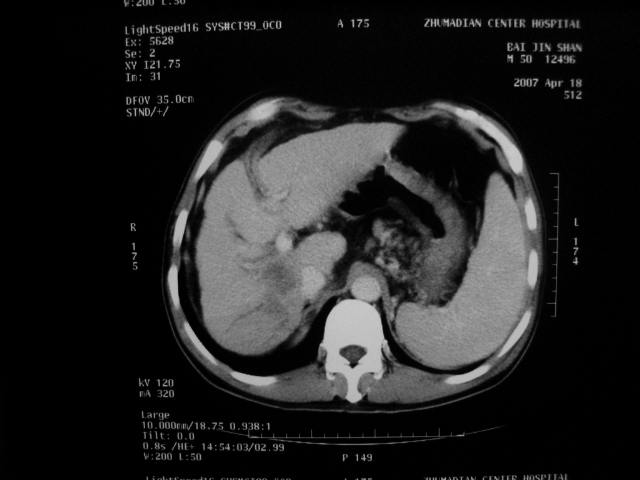

标题: CT7751:病人,50岁,肝硬化多年,行CT三期扫描 [打印本页]

标题: CT7751:病人,50岁,肝硬化多年,行CT三期扫描

拟;1)乏血供小肝癌.淋巴结转移。

2)肝硬化。

肝硬化 脾大 胃底静脉曲张 肝癌 门腔间淋巴结肿大

1、肝右叶低密度灶考虑肝癌

2、肝硬化

肝硬化、脾大,静脉曲张,肝右叶低密度灶,增强无明显强化,还是考虑肝癌可能性大,建议结合afp检查。

考虑肝硬化,脾大,静脉曲张,肝右叶低密度灶,右肝癌可能性大。